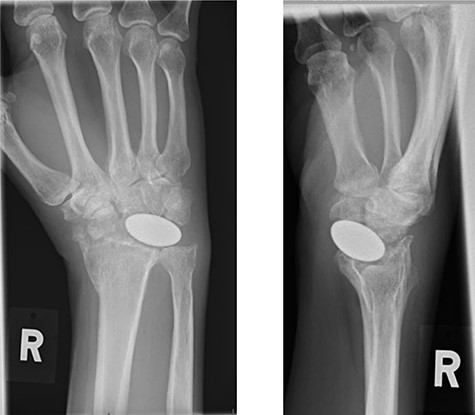

Radiographs demonstrated that the Pyrocarbon implant was palmarly displaced and rotated 90 degrees; it had migrated into the carpal tunnel/ distal forearm (Fig. 2). The clinical diagnosis was compression of the ulnar due to the migration of implant. Surgery was carried out 1 month later during which the Pyrocarbon Amandys wrist implant was removed through a volar approach (Fig. 3) and total wrist fusion was performed using a straight Arbeitsgemeinschaft für Osteosynthesefragen (AO) wrist fusion plate (Fig. 4). The surgery successfully relieved all wrist pain and was accompanied by prompt resolution of symptoms of ulnar nerve compression; she was discharged from follow-up approximately 3 months after surgery.

Post-operative radiographs following removal of pyrocarbon implant and total wrist fusion.